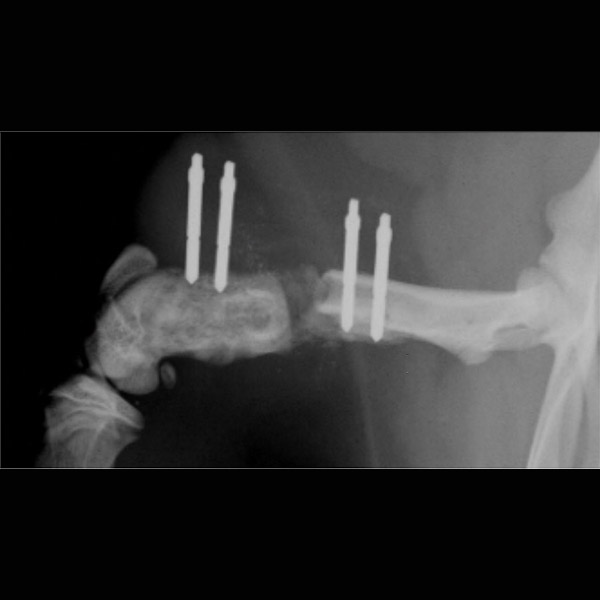

In der geplanten Studie soll nun die Bewegung der Fibula zur Tibia hin in einem bereits in Vorversuchen entwickeltem Projektaufbau an einem 6-Achsen-Industrieroboter unter kontinuierlicher Belastung und Bewegung schrittweise unter Durchtrennung und Rekonstruktion der Syndesmosenregion untersucht werden (Siehe Abbildung 1). Hierbei wird zunächst ein hinteres Kantenfragment osteotomiert sowie im Folgeschritt eine ligamentäre Durchtrennung des vorderen und interossären Syndesmosenblattes präpariert. Im dritten Schritt wird das hintere Kantenfragment durch eine Plattenosteosynthese rekonstruiert. Gegenübergestellt werden in weiteren Versuchsschritten dann die additive Augmentation des vorderen Syndesmosenblattes mit einem SutureTape Fadenanker im Vergleich zur fibulotibialen Stellschraube sowie die Kombination aus beiden Verfahren bis hin zum Load to Failure Test (Siehe Abbildung 2). Ziele der Studie sind zum einen die Untersuchung der Kinematik der Fibula im physiologischen, instabilen sowie dorsal rekonstruierten Zustand, da erste Ergebnisse auf eine persistierende Rotations- und Sagittalinstabilität der Fibula nach Osteosynthese des hinteren Kantenfragmentes hindeuten. Zum anderen soll die Biomechanik und Stabilität einer neuartigen additiven anatomischen Rekonstruktion des vorderen Syndesmosenblattes im Vergleich zur konventionellen Stellschraube untersucht werden. Unsere Hypothese ist folgende: Die OSG-Kinematik wird durch eine Augmentation des vorderen Syndesmosenblattes mit einem anatomisch verlaufenden Fadenanker im Vergleich zur extraanatomischen Stellschraube physiologischer wiederhergestellt.